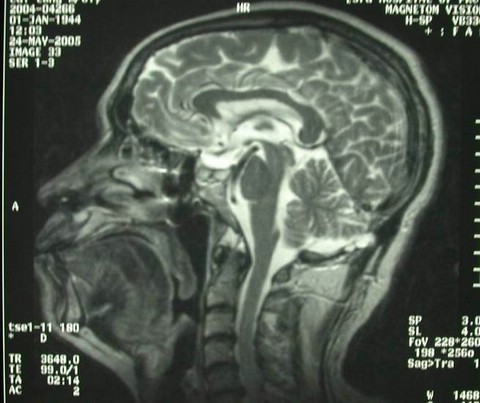

男性,60岁,主因双眼视力下降2个月入院,查MRI示:鞍区巨大占位。

诊断考虑垂体腺瘤。行经鼻蝶手术,全切肿瘤,术后复查如下: